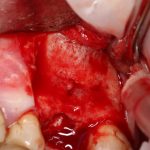

Наложение швов.

Если на этапе разреза и формирования раны всё сделано правильно, то наложение швов не вызывает особых трудностей. Периостотомия или послабляющие разрезы на периосте не требуются (ни практически никогда не требуются). А сами швы получаются аккуратными и герметичными:

Обрати внимание, что все шовные лигатуры находятся в пределах кератинизированной десны. Это позволяет избежать деформации тканей и лишних рубцов. В наиболее уязвимых местах (около зубов) шовные лигатуры лучше продублировать.